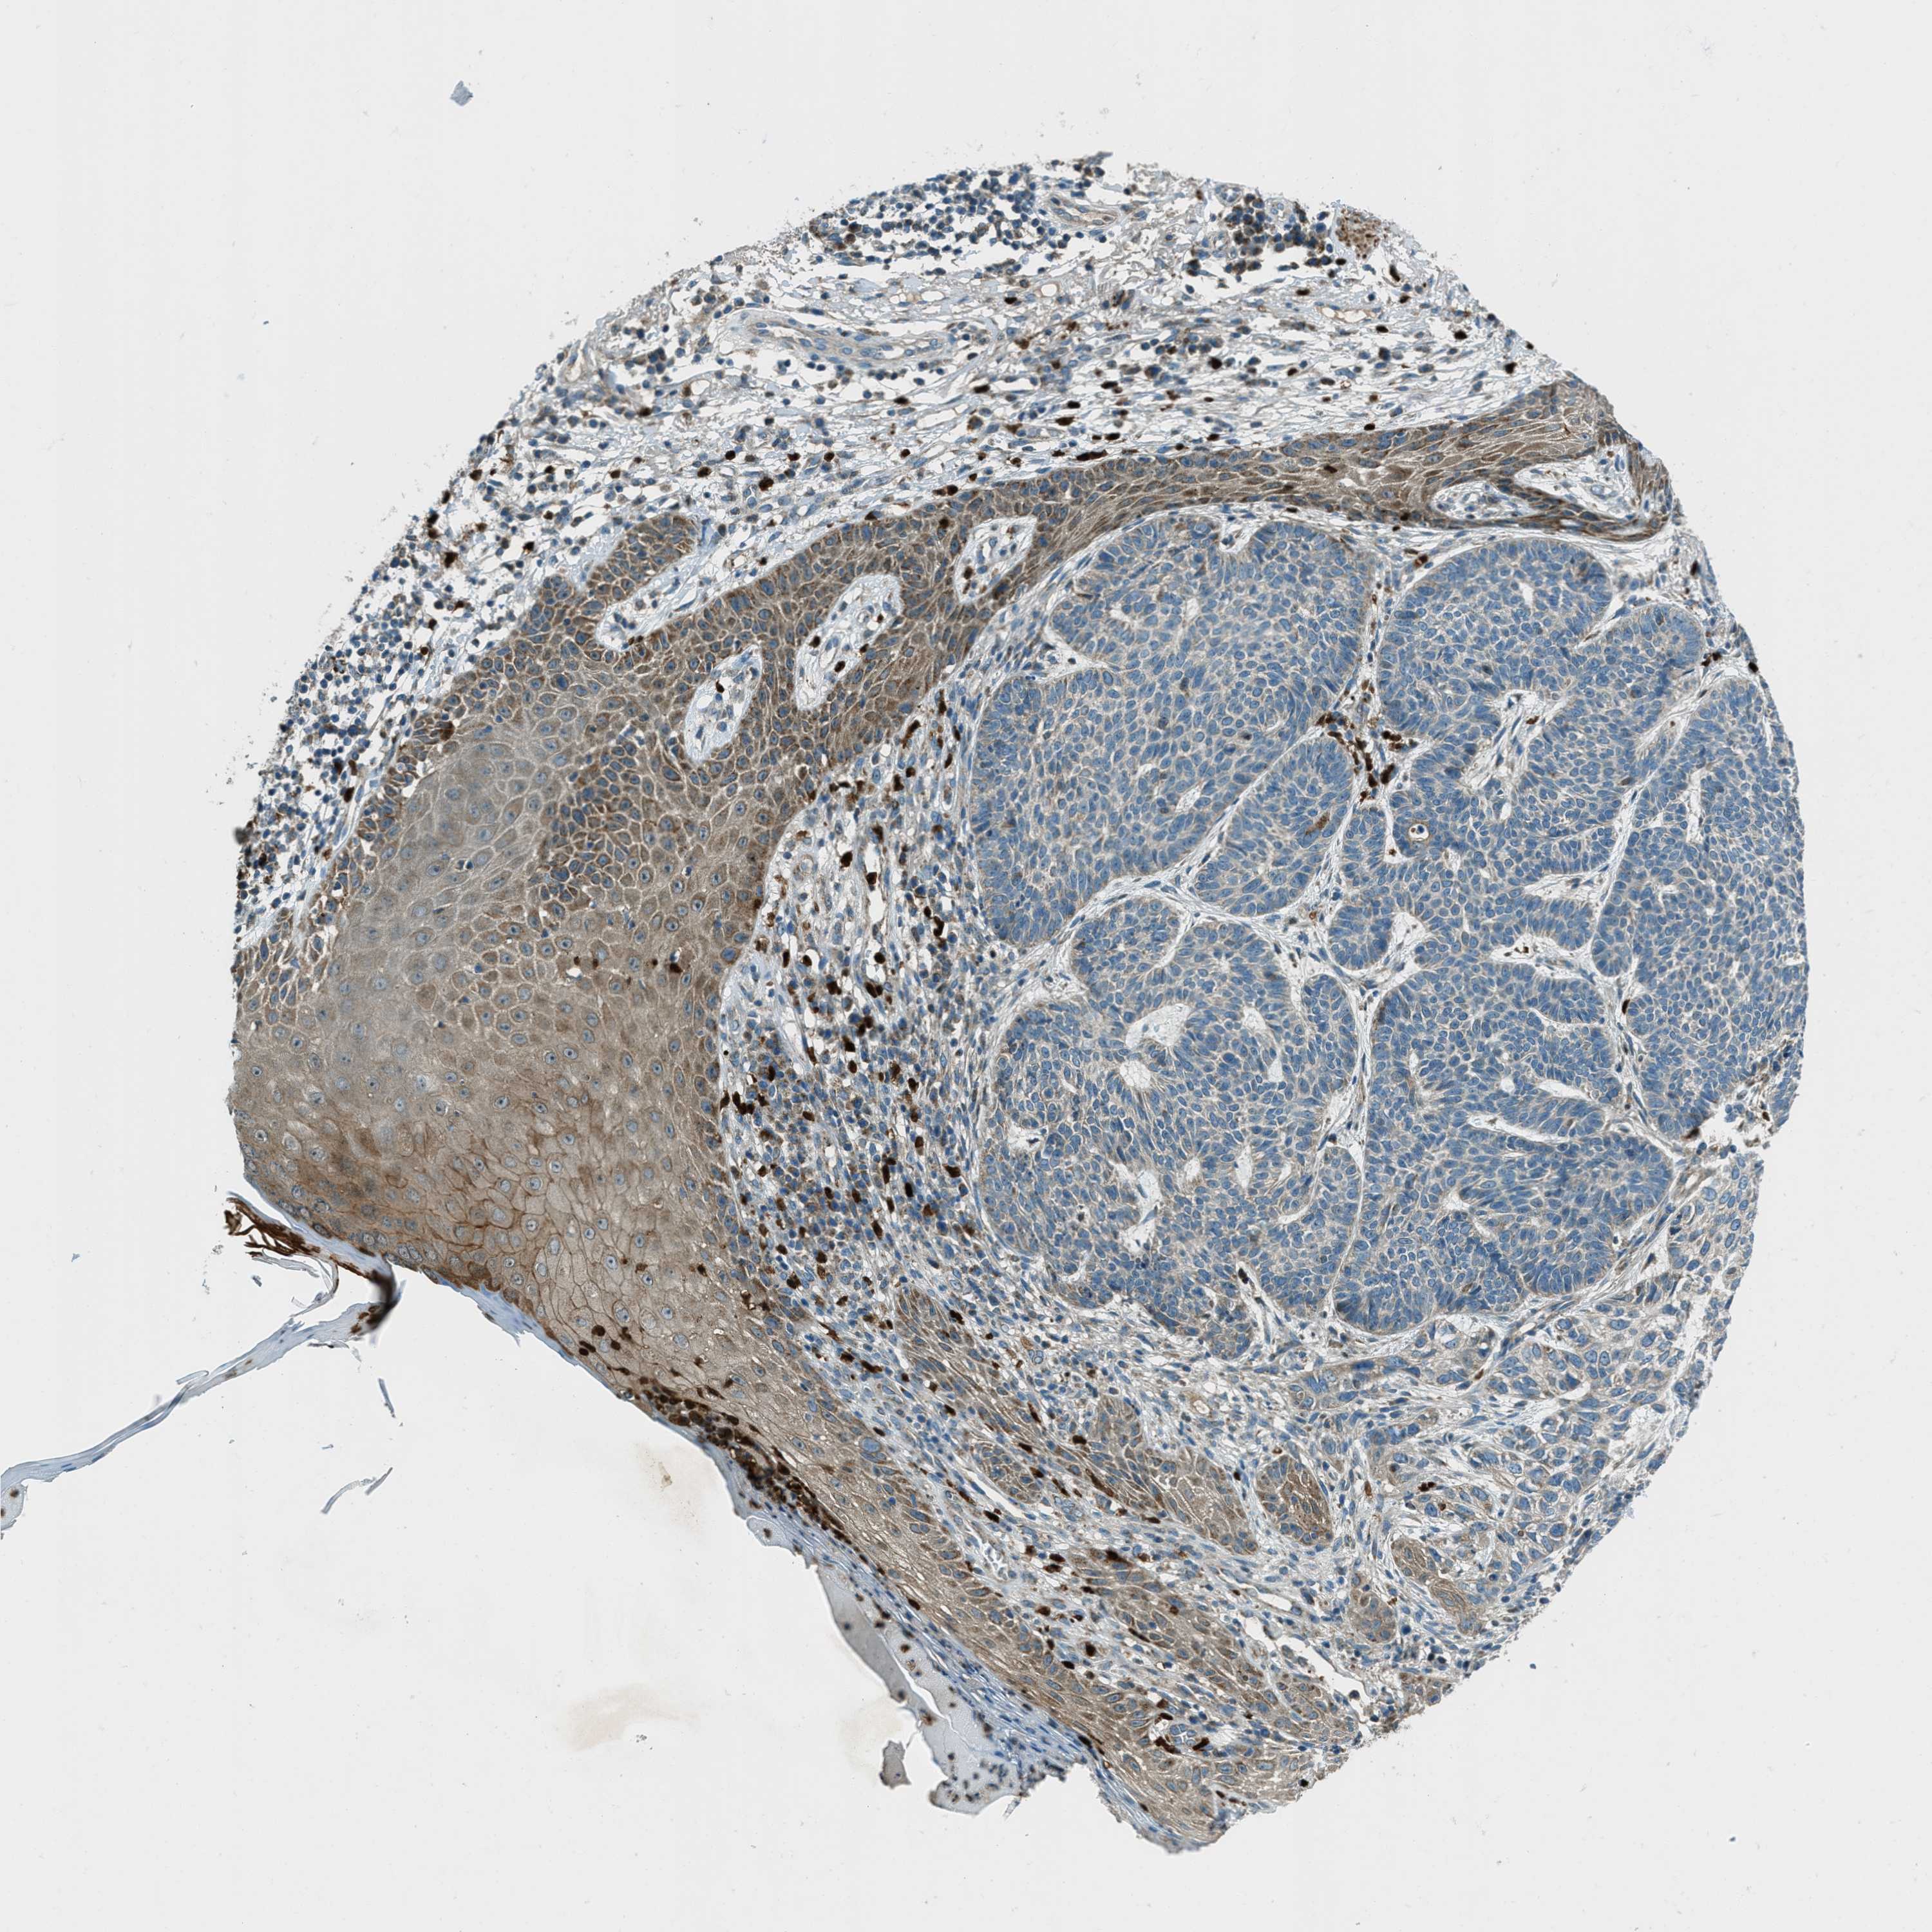

SKIN CANCER - Protein expressioni

A mouse-over function shows sample information and annotation data. Click on an image to view it in a full screen mode. Samples can be filtered based on level of antibody staining by selecting one or several of the following categories: high, medium, low and not detected. The assay and annotation is described here.

Each image is clickable and will lead to virtual microscopy that enables deeper exploration of all samples and also displays staining intensity scores, fraction scores and subcellular localization as well as patient and tissue information for each sample.

Antibody HPA017322

Staining

High

Intensity

Strong

Quantity

>75%

Location

Nuclear

Squamous cell carcinoma in situ, NOS

Squamous cell carcinoma, NOS

Squamous cell carcinoma, metastatic, NOS

Basal cell carcinoma